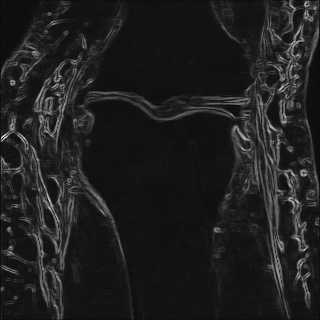

6.2.2 Quality of the Predicted Edges

EPN is utilized to provide edge priors for later reconstruction, so the quality of the predicted edges is very important. In Fig. 10, we provide some qualitative results of the predicted edges of EPN on three multi-coil datasets. Among them, the GT edges are extracted using the Sobel operator. As can be seen from the images, our proposed EPN can predict an approximate contour for the overall subject and can reconstruct accurate edges close to the GT edges under two acceleration factors. This fully verifies the effectiveness and excellence of the proposed EPN.